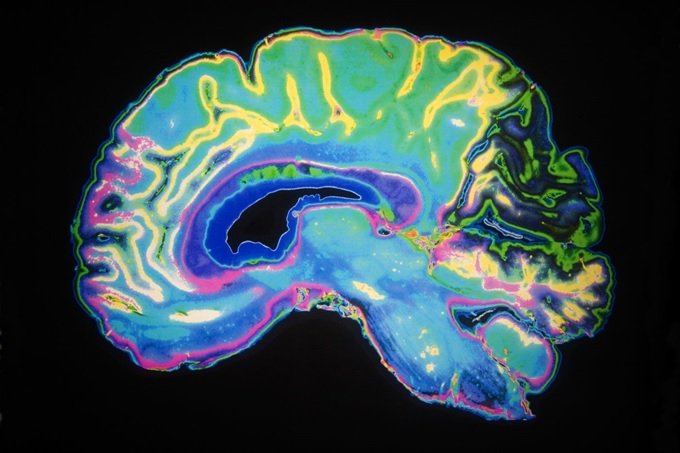

گروهی از پژوهشگران MIT به تازگی موفق به شناسایی دو پیوند عصبی در بخش آمیگدال مغز شدهاند که وظیفه پردازش احساسات مثبت و منفی را دارد. این گروه در آزمایش خود، تعدادی از سلولهای عصبی کشف شده را با نوعی پروتئین حساس به نور نشانهگذاری کردهاند و کشف کردهاند که این عصبها اقدام به ساخت کانالهای موازی و پیچیدهای میکنند که واکنشهای متفاوتی را بر اساس شرایط مختلف از خود نشان میدهند. تعدادی از عصبهای قرار گرفته در این پیوندها بر اساس حس مشخصی هیجانزده میشوند، در حالی که عصبهای دیگر از بهروز آن احساس ممانعت به عمل میآورند. زمانی که این واکنشها در یک کانال مشخص با یکدیگر ترکیب میشوند، باعث پدید آمدن احساسی میشوند که شما در یک لحظه آنرا تجربه میکنید.

در مطالعهای که در گذشته انجام شده بود، آزمایشگاه Tye دو گروه از سلولهای عصبی درگیر در زمینه پردازش احساسات مثبت و منفی را شناسایی کرده بود. یکی از این گروههای عصبی برای رله کردن اطلاعات به ﻧﻮﻛﻠﺌﻮس اﻛﻮﻣﺒﻨﺲ (nucleus accumbens) که در یادگیری و دنبال کردن تجارب نقش مهمی بازی میکند، ارسال میشود. در حالی که عصب دوم برای ارسال ورودی به بخش آمیگدال مورد استفاده قرار میگیرد. در مطالعه جدید، دانشمندان به دنبال پیدا کردن این جواب هستند که نورونها در عمل و بر مبنای غریزه حیوانی به یک محرک ترسناک یا لذتبخش چه واکنشی از خود نشان میدهند.